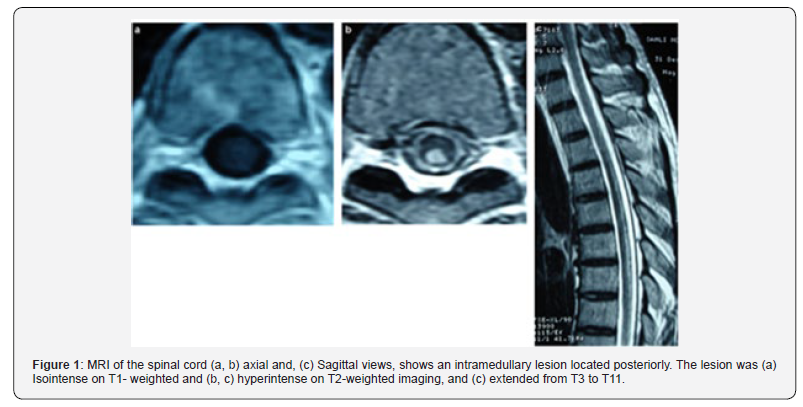

MRI has been considered the exam of choice (Figure 1) for detecting B12 deficiency-related central nervous system involvement and for excluding possible mimics. Imaging of the spinal cord in cases of severe myelopathy that are notinitially recognized as the result of vitamin B12 deficiency, had characteristic hyperintensity on T2-weighted imaging, described as an inverted V-shaped pattern in the cervical and thoracic spinal cord [6]. Brain involvement has been reported in B12 deficiency. Vitamin B12 deficiency has been also associated with attention deficits, acute mental-status and acute cognitive changes, with electroencephalography abnormalities. In an individual patient with dementia and Cbl deficiency, the response of the cognitive complaints to Cbl administration is variable and may relate to duration of deficiency. This relationship between cognitive decline or cognitive deficits and Cbl deficienc has been studied not only with vitamin B12 levels but also with HomoCysteine (Hcy) or MMA levels, holo Transcobalamin (TC) levels, and vitamin B12 intake. Observational studies have shown that high total Hcy increases the risk of cognitive impairment with or without dementia. HHcy cause agonism of N-methyl-D-aspartic acid receptors, leading to DNA damage and apoptosis, inhibition of hippocampal neurogenesis, decreased of gamma-amino-butyric acid-mediated inhibitory function and endothelial cell toxicity [23,24].

Low levels of vitamin B12 have been associated with neurocognitive disorders. This evidence-based analysis assessed the usefulness of serum vitamin B12 testing as it relates to brain function. Based on low to moderate quality of evidence, treatment with vitamin B12 and folate in patients who have mild cognitive impairment seems to slow the rate of brain atrophy compared with patients who have mild cognitive impairment receiving a placebo. Whether this translates into clinical benefit is unknown [22]. A recent metanalyses conducted by Ford AH [25,26], showed that raised total plasma homocysteine is associated with an increased risk of cognitive impairment and dementia, although available evidence from randomized controlled trials shows no obvious cognitive benefit of lowering homocysteine using B vitamins [27,28]. However, assessing vitamin B12 levels in patients with cognitive impairement or as part of work up of dementia is recommended. Radiologic aspects of low vitamin B12 or Hc include periventricular leukoencephalopathy, manifested as white matter hypodensity on CT scan or hyperintensity on T2 weighted MRI. A brain atrophy and silent brain infarcts. Other, neurological disorders also described such as cerebellar ataxia, abnormalities of cranial nerves, Parkinsonian syndrome, mood disturbance (depression and mania) and movement disorders [4,6,9].